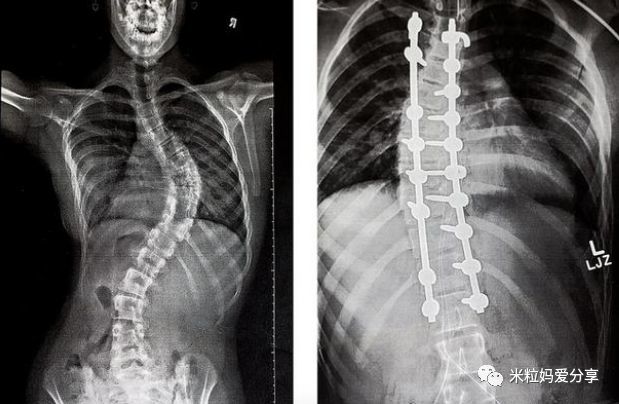

但遗憾的是,经过几年的治疗后,发现脊柱侧弯并没有任何好转,所以必须要接受手术治疗。

手术过程非常疼痛,得用钢钉做固定,然后与骨头相结合,光想想都疼啊!恢复过程超过两个月。

好在,经过手术治疗,小女孩慢慢恢复了正常。